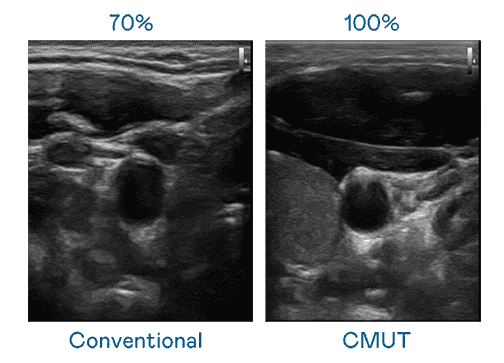

CMUT 技术是一种用电容式微机电元件来产生超音波讯号的技术。。与传统 PZT 压电式技术相比,,,,CMUT 频宽增加 30%,,,,更宽频的超音波讯号让影像解析度大幅提升,,,是实现高影像品质医疗超音波扫描、、促进精准医疗发展的关键技术。。。

大频宽带来超清晰影像

超音波影像的解析度高低,,,,首先取决于探头能发出的讯号频宽。。。。万利 CMUT 可提供高清晰的超音波讯号,,,提供高频宽、、高灵敏度、、、、影像纹理细节更高的超音波影像,,,,协助医护人员缩短影像判读时间及利用精准的医疗影像进行诊断。。